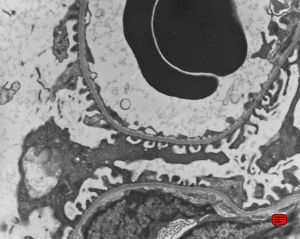

normal kidney - mouse(endothelium and podocytes)

normal kidney - mouse(endothelium and podocyte)